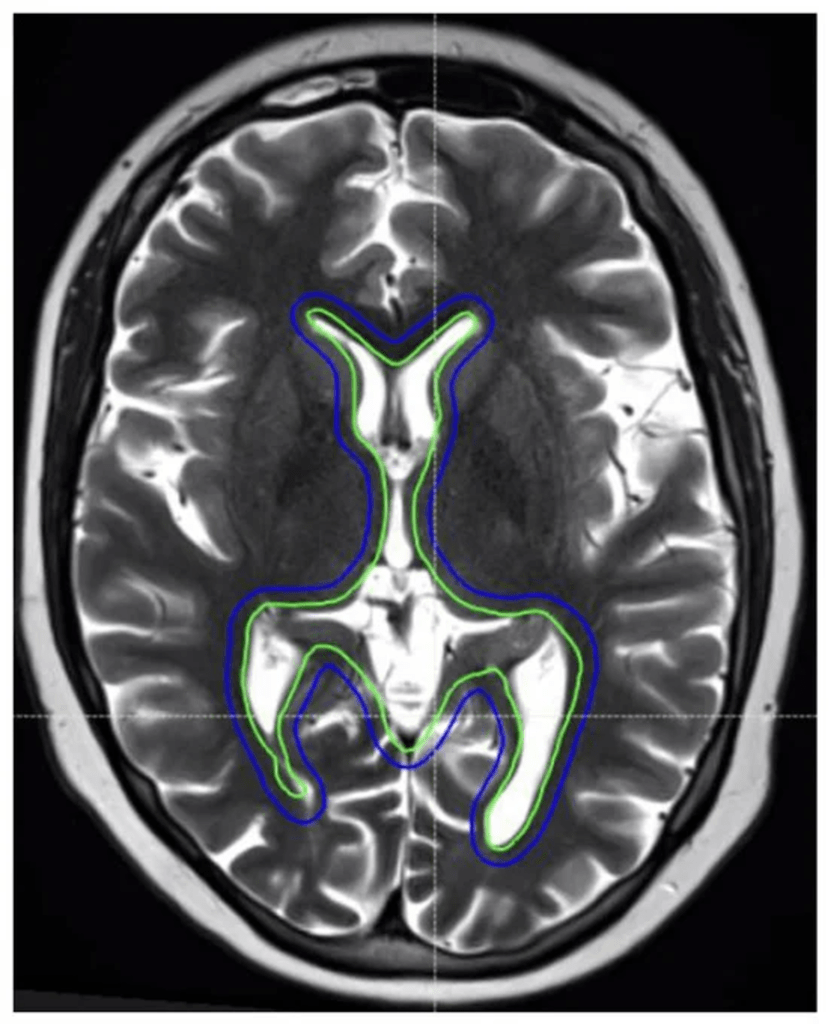

Figure 2. An 11-year-old female patient with intracranial germinoma. The intracranial RT target volumes are shown as follows: whole ventricular RT CTV (green) and 3 mm PTV geometric expansion (blue).

Intracranial radiotherapy can have a significant impact on neurocognitive functions, particularly memory formation and learning. Memory formation is a complex and dynamic process involving multiple anatomic compartments of the brain, with the hippocampus being one of the critical structures responsible for this function [150]. Basic science studies have demonstrated that radiation exposure can lead to a decline in neural stem cells and increased inflammation in the hippocampal region [151,152]. Observational and single-arm prospective studies have further shown a correlation between the mean radiation dose to the hippocampus and the development of short-term memory and learning impairments in adults [153]. The hippocampal avoidance (HA) RT technique, designed to minimize radiation exposure to the hippocampi while ensuring adequate coverage of the remaining brain, has been proposed as a strategy to mitigate the risk of neurocognitive decline (Figure 3).

Figure 3. An example of the hippocampal−sparing whole brain radiotherapy plan. Grey shade represents the hippocampus, which is spared from a full dose of radiotherapy [154].

A prospective randomized trial demonstrated that, in adult patients receiving whole-brain radiotherapy (WBRT) for brain metastases, HA techniques that reduce the mean hippocampal dose result in significantly less deterioration in executive function, learning, and memory, without compromising tumor control [155].

In the pediatric CNS setting, there have been no prospective randomized trials to establish the effectiveness and safety of hippocampal avoidance (HA) RT. However, several pediatric studies have demonstrated a correlation between the RT dose to the hippocampi and memory outcomes. Zureick et al. found that children treated with PBT for primary brain tumors who received higher doses to the left hippocampus experienced worse visual and verbal memory outcomes [156]. Another study from the Hospital for Sick Children reported associations between hippocampus dose and verbal comprehension across different types of pediatric brain tumors treated with RT [157]. Similarly, Acharya et al. demonstrated that, for the children and young adolescents treated with RT for low-grade glioma (LGG), a higher hippocampal dose was associated with worse neurocognitive outcomes [158]. Overall, the most recent literature suggests that reducing the mean dose and volume of both the right and left hippocampus to 20–40 Gy may translate to better cognitive preservation. A summary of select literature on the hippocampus dosimetry correlation with the cognitive outcome is outlined in Table 3.